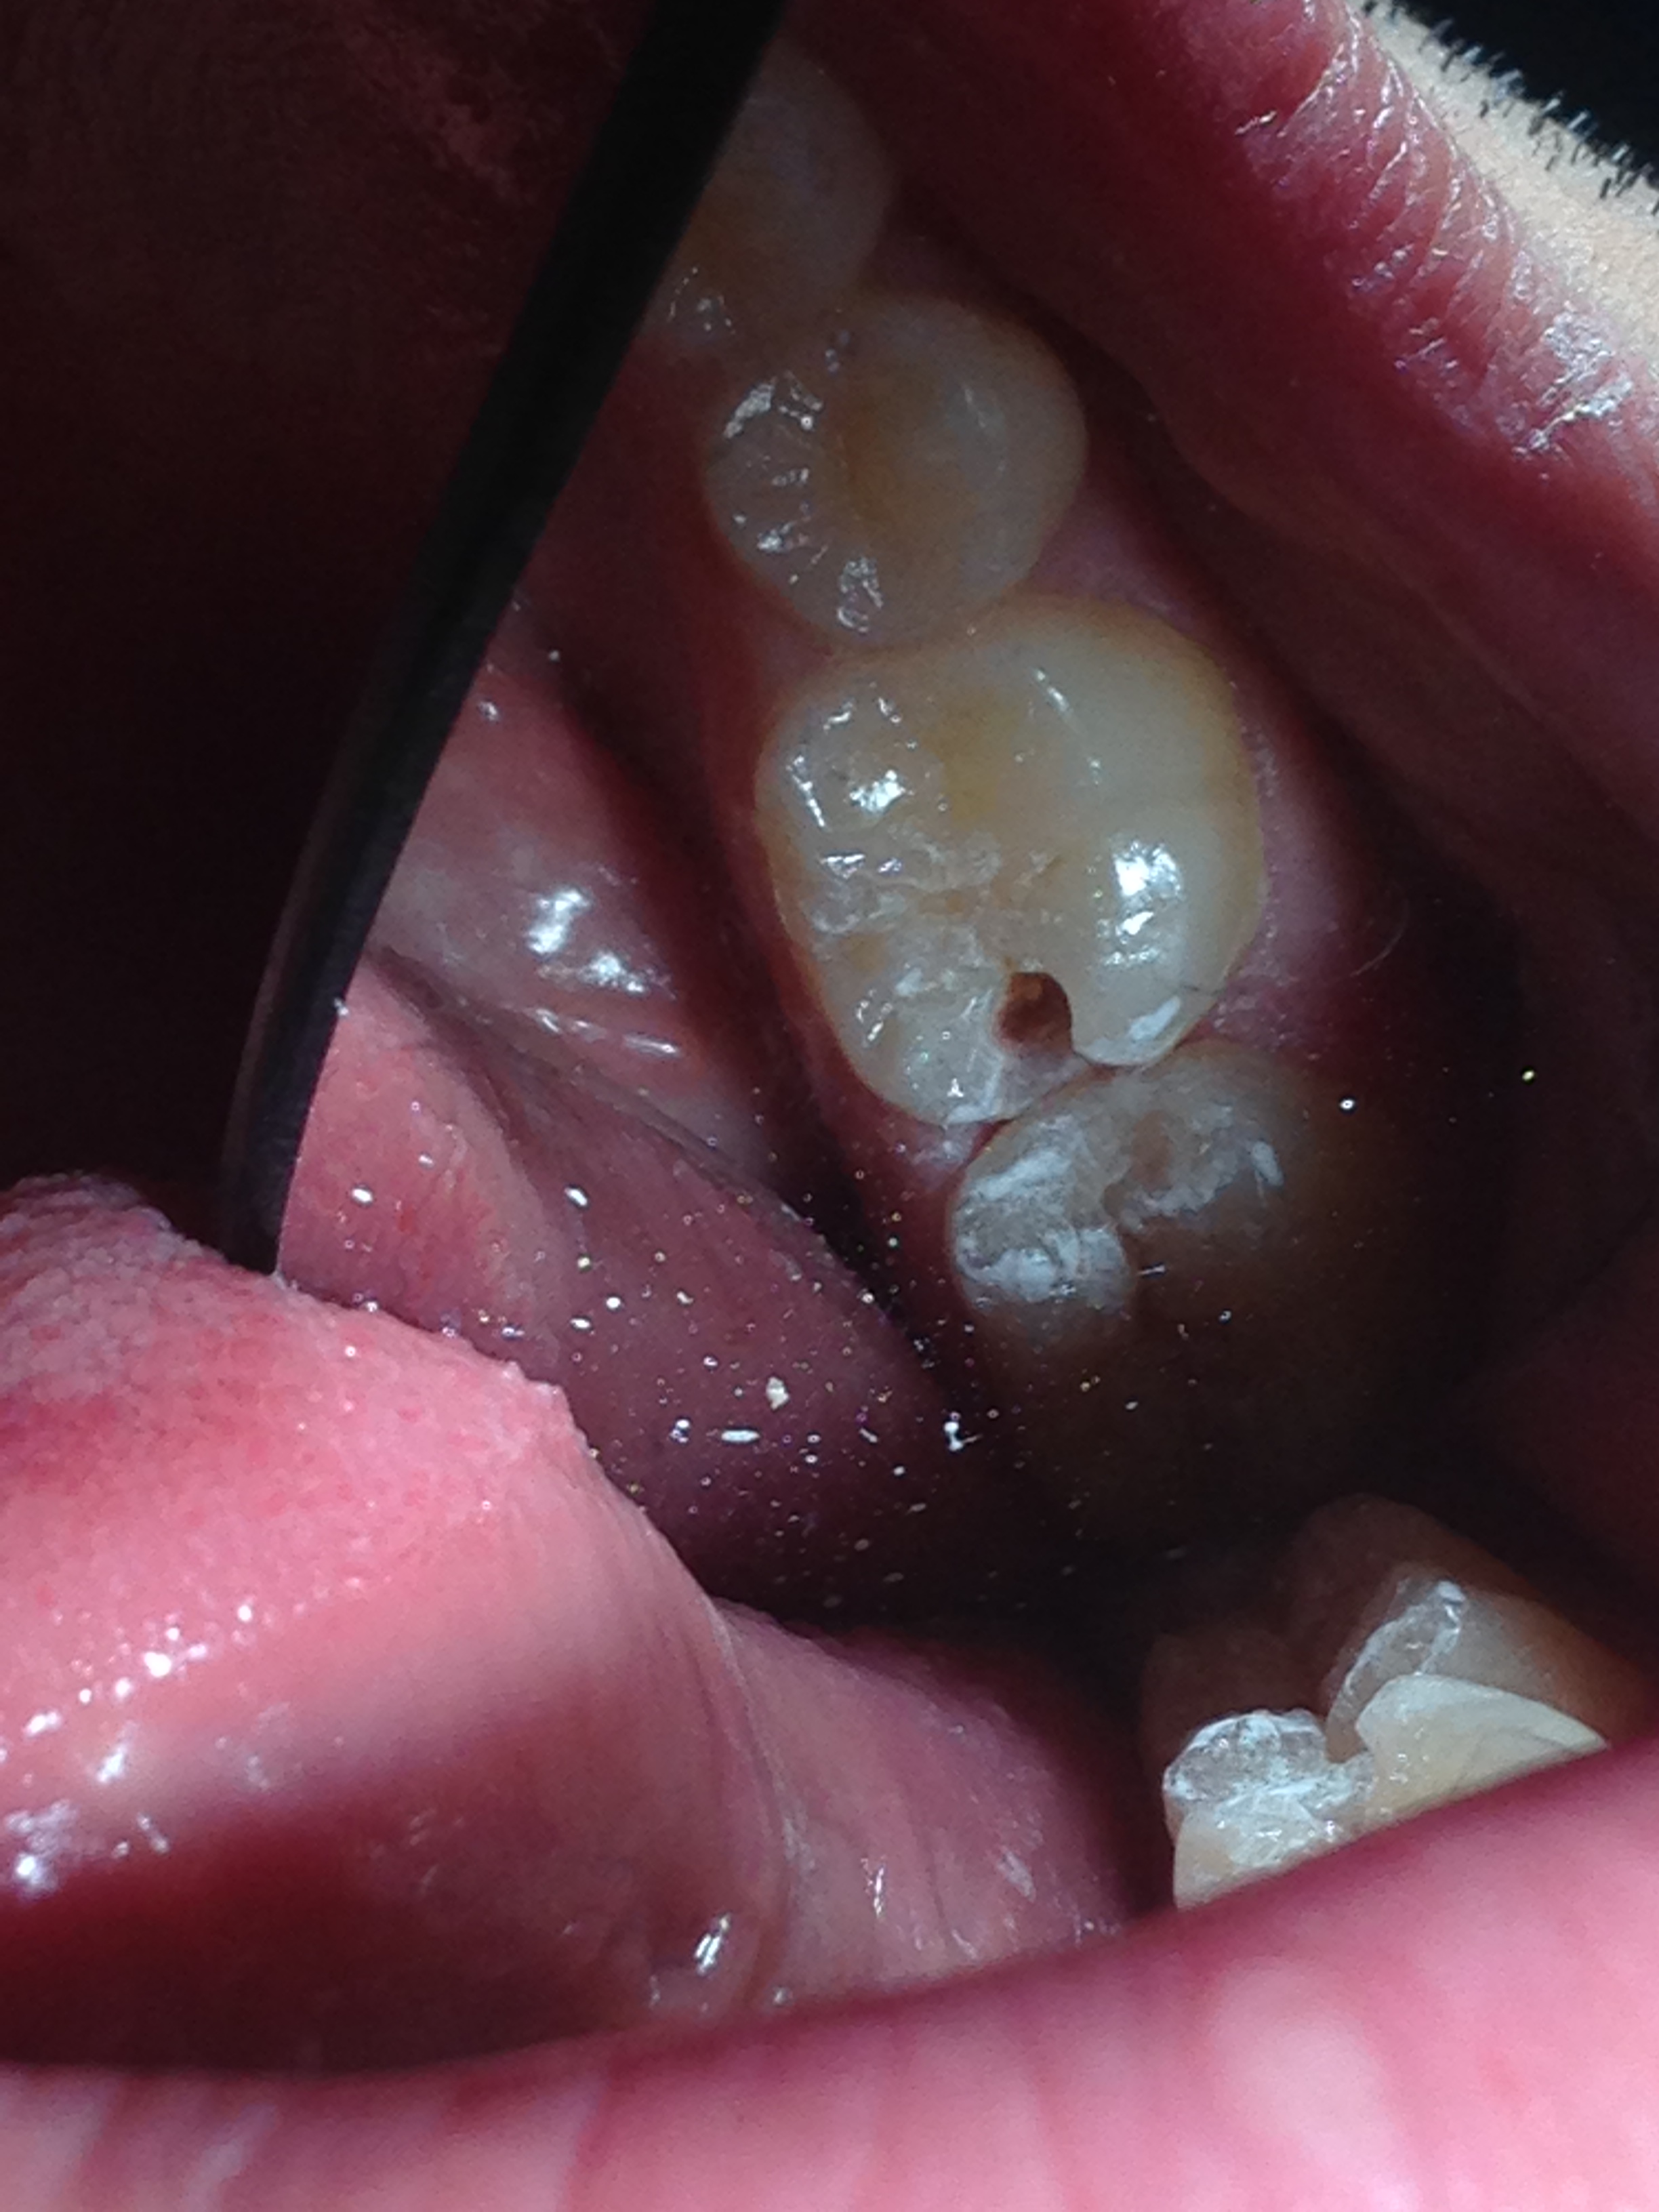

L'odontoiatria conservativa è un particolare ramo che tratta il restauro e la cura di tessuti cariati o danneggiati irreparabilmente.

Il procedimento classico è quello della semplice chiusura del foro nel caso in cui si tratti di una carie o, in presenza di un elemento scheggiato si agisce ricreando nei minimi dettagli l'originale anatomia del dente. In entrambe le situazioni si usa il composito, materiale che ha come fiore all'occhiello la minima invasività grazie alla sua forte adesione ai tessuti dentali; inoltre il colore e la resistenza alla masticazione renderanno il dente curato indistinguibile da uno sano.